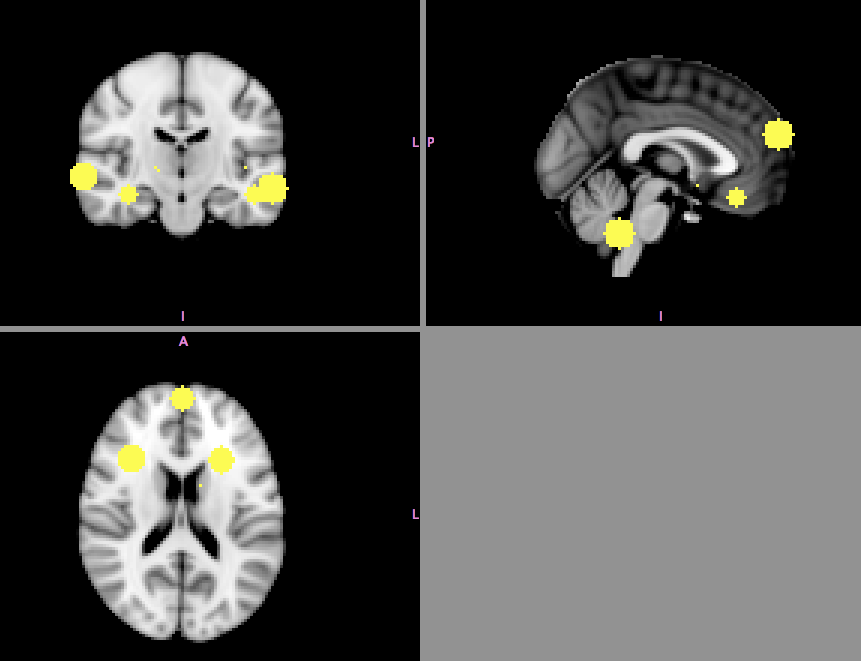

| X | Y | Z |

|---|---|---|

| 12 | 57 | -6 |

| 33 | 21 | 15 |

| 24 | -6 | 51 |

| 28 | 10 | 18 |

Yarkoni et al, 2011, Nature Methods

Gorgolewski et al., 2015, Frontiers in Neuroinformatics